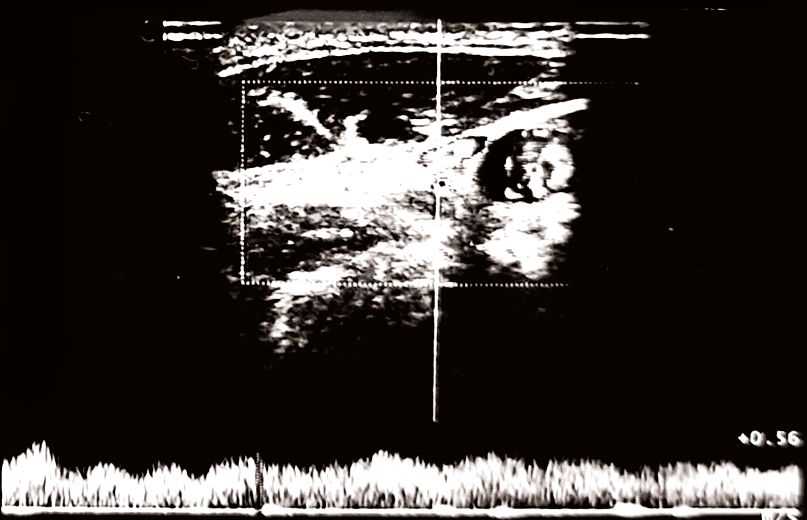

Echo-color Doppler: regular supra-aortic vessels, IMT 0.7 mm, no carotid lesions. Altered jugular system: right jugular “bottleneck” (middle third), reduced, poorly phasic flow; left jugular compressible (Figure 1(A)). Patent vertebral axes. Findings compatible with CCSVI.

Follow-up Doppler showed progressive improvement. Initial findings are presented in Figure 1: right jugular “bottleneck,” reduced flow; compressible left jugular. By week four, improvement was noted in both, and after eight weeks of treatment (Figure 1(B)) and two additional maintenance sessions, the 16 week-follow-up (Figure 2(A)) venous normalization. By 24 weeks (Figure 2(B)): maintained normalization, stable IMT. Clinically: headache resolved (2 - 3/week to 0); FSS-9 5.6 to 3.1; PSQI 9 to 5; VAS 7 to 2; SCM PPT +45%; cervical mobility +35%. Minor side effects were reported, as mild pain (2/8 initial sessions), resolving haematomas. Maintained improvements at follow-ups, with limited exercise adherence, suggest DN’s primary benefit.

(A)

(B)

Figure 1. (A): At Time 0 (baseline examination, prior to the initiation of Dry Needling treatment), the carotid arteries presented with regular vascular walls, an IMT of 0.7 mm, and no significant atherosclerotic plaques. However, the jugular venous system showed signs of altered drainage. The right jugular vein exhibited an evident “bottleneck”, or functional stenosis, in the middle third, accompanied by reduced and poorly phasic flow. The left jugular vein presented with a compressible lumen and hypodynamic flow. These findings were deemed compatible with a diagnosis of CCSVI. (B): After 8 weeks of Dry Needling treatment, a follow-up examination was conducted. The carotid arteries remained unchanged, with a stable IMT and no significant alterations. In the jugular system, the right jugular vein showed a less pronounced functional stenosis compared to Time 0, with evidence of partial flow recovery. The left jugular vein demonstrated improved compressibility and a more regular flow pattern. These findings indicated signs of improved venous drainage, specifically a reduction in the right jugular obstruction.